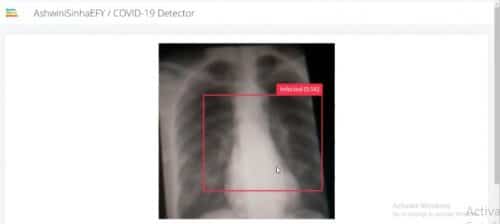

X-Ray-Based Quick COVID-19 Detection With Raspberry Pi

General X-Ray-based Covid-19 detection systems are fast and give quick results along with the status of how much the COVID-19 virus has infected the lungs. Previous Covid-19 detection systems took time to give reports while the infected person needed immediate attention. Also, all such detection systems used parts that required to be disposed of after … Continue reading X-Ray-Based Quick COVID-19 Detection With Raspberry Pi